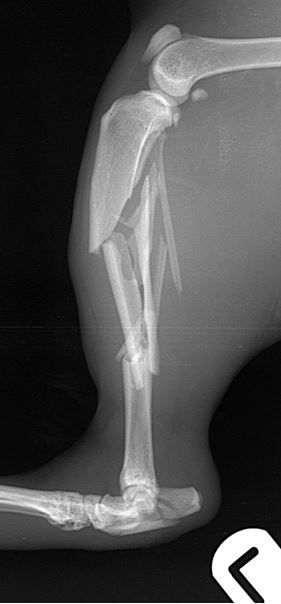

Fig. 1 A 6-year-old DSH cat with comminuted fractures of the tibia, fibula and calcaneus